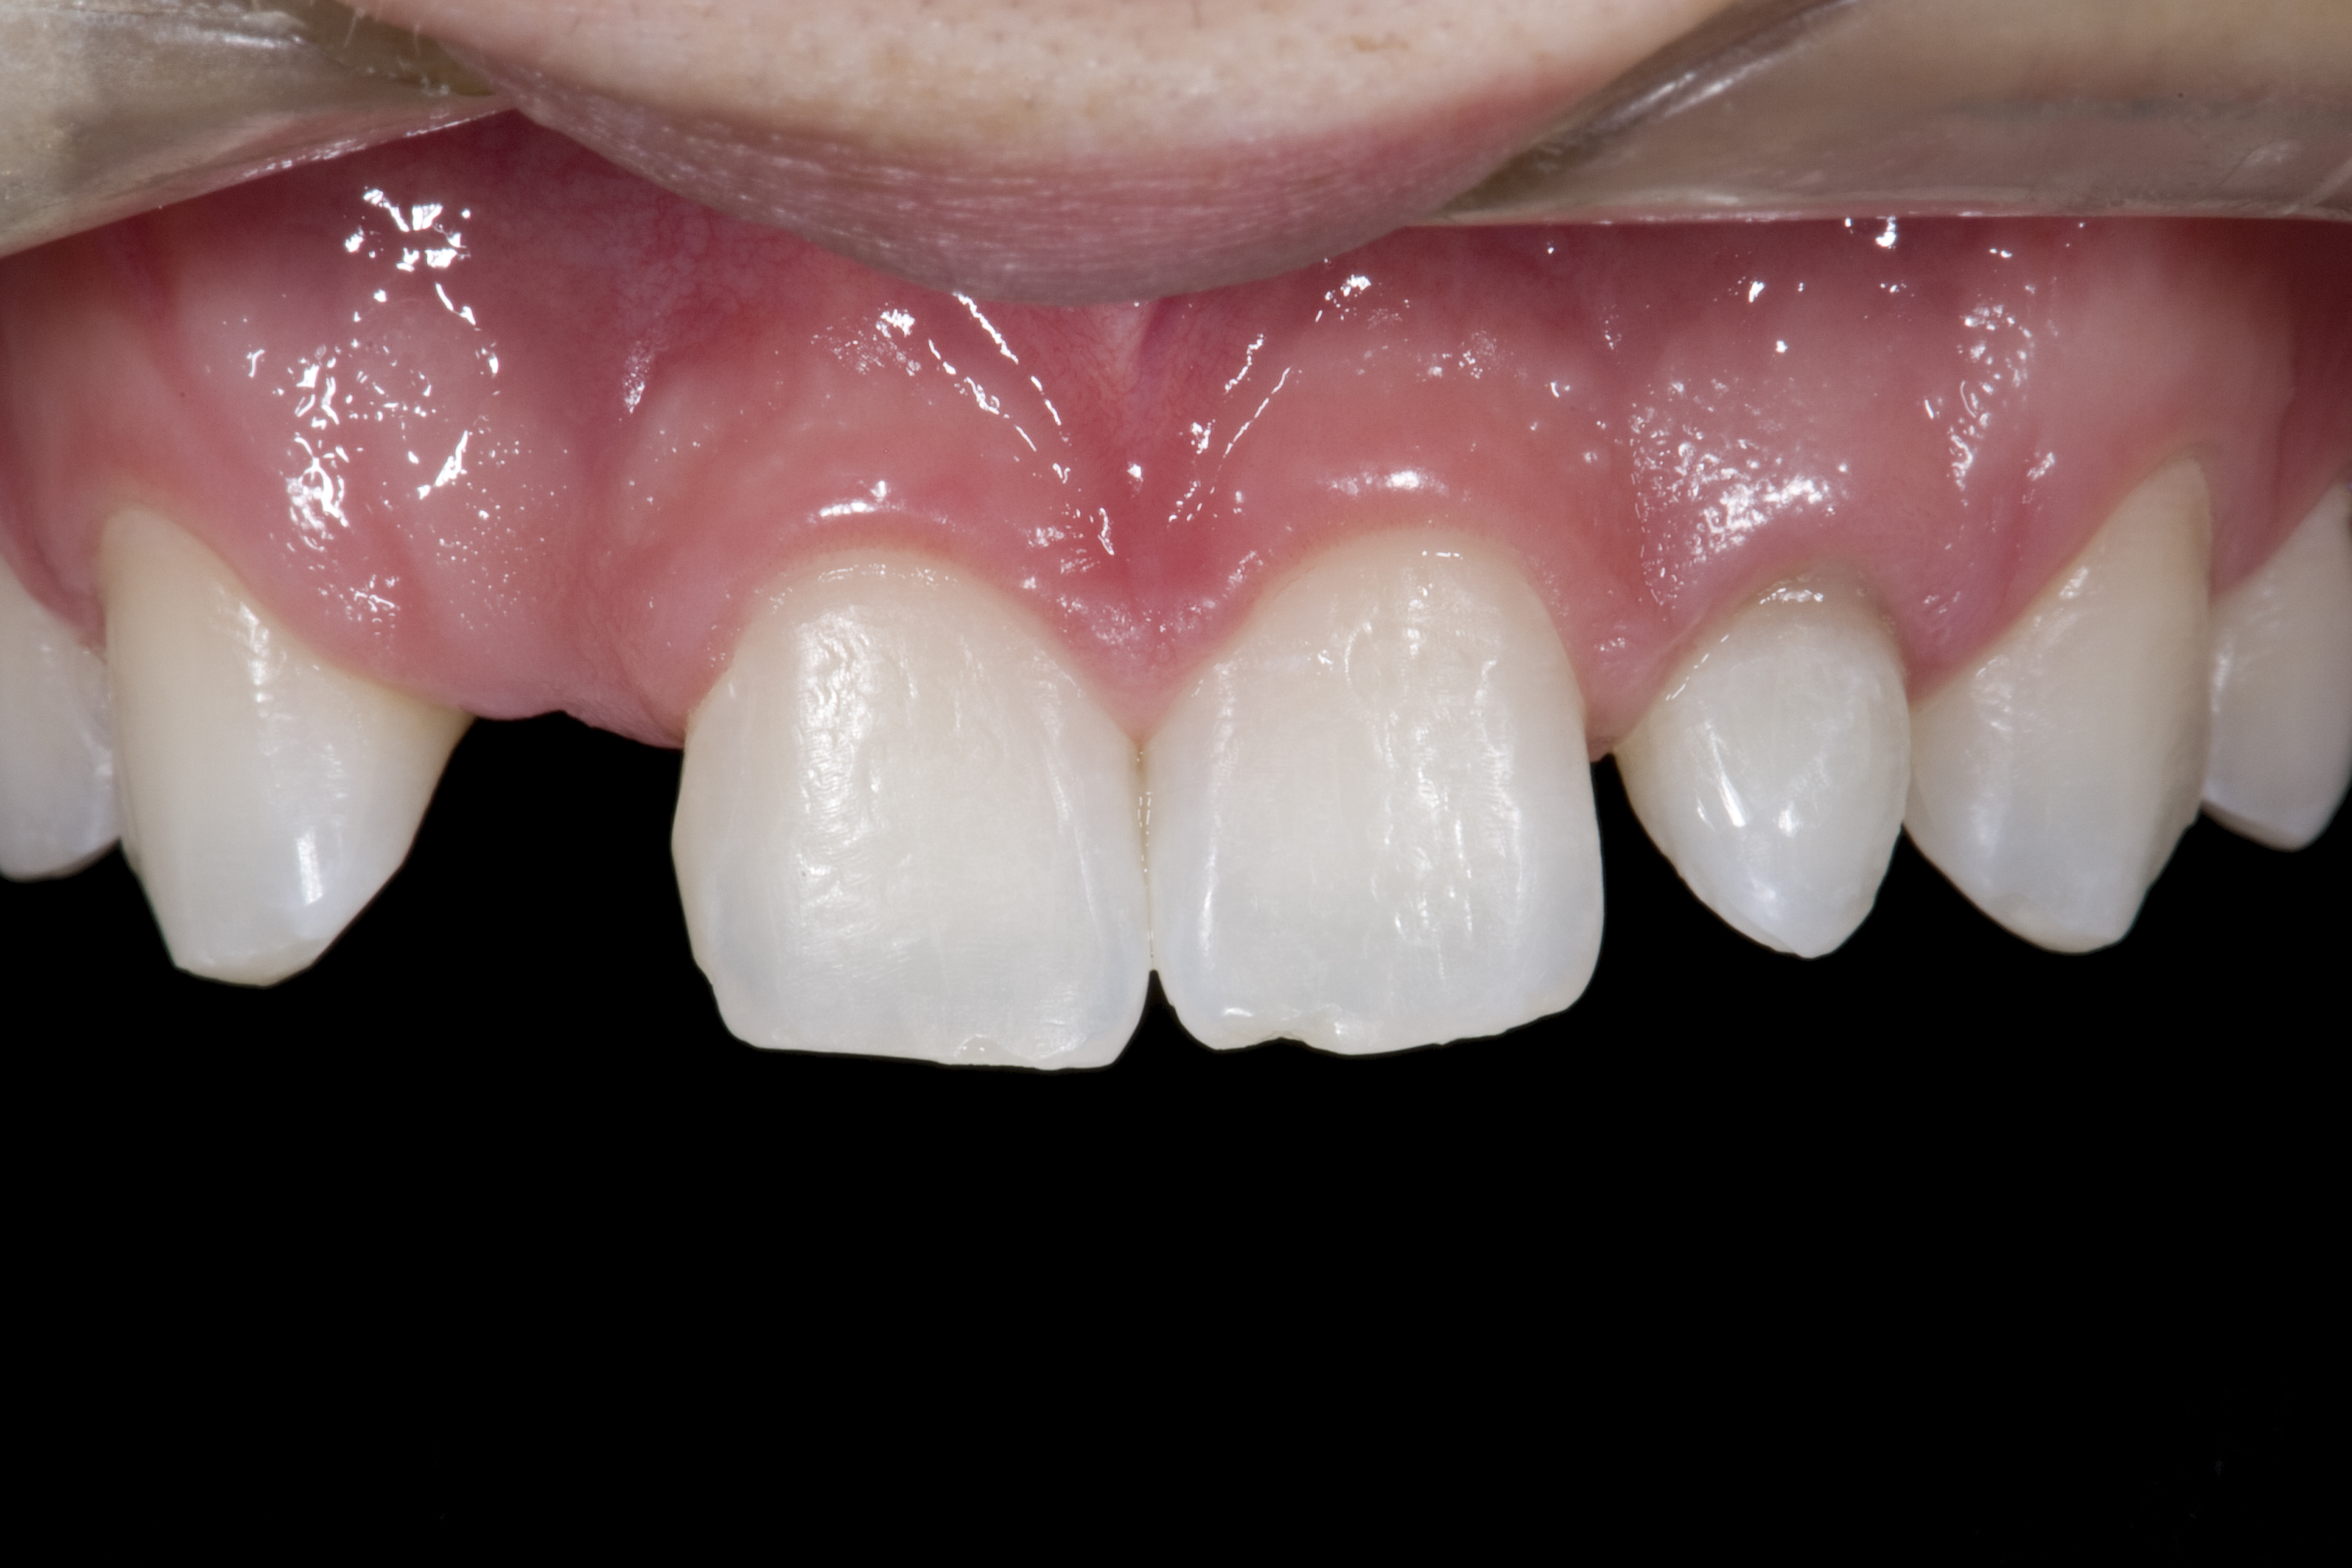

(12.) 15-year-old girl after orthodontic therapy idealized maxillary lateral incisor spaces.

Figure 12

(13.) Deficient ridges in the areas of the missing lateral incisors.

Figure 13

(14.) Occlusal view. Some form of augmentation would be needed if implants were being considered.

Figure 14

Some patients do not want an implant due to the need for surgical intervention, and others may not have enough space for implant placement. A 15-year-old patient presented to the office after completion of orthodontic treatment to idealize the spacing of her teeth and improve her occlusal relationship (Figure 12 through Figure 14). Because both of her maxillary lateral incisors were missing, the patient was wearing a retainer with lateral incisor pontics. She had a busy school schedule, but expressed her desire for a fixed restorative option. All of her options were discussed, and the patient was informed that if she wanted an implant, she would have to wait for at least 3 to 4 years for completion of growth. The patient was not sure if or when she wanted to have an implant placed in the future, especially considering her busy schedule and desire to attend college after high school. Considering her age and the need to be conservative, a single-wing zirconia Maryland Bridge was chosen as the ideal prosthetic replacement option. Because bonding a non-etchable and smooth surface such as zirconia requires chemical adhesion, it was decided to use a modified technique to make the bridge more retentive. One of the ways to improve adhesion of a zirconia bridge is to use an etchable feldspathic ceramic layer on the internal surface of the zirconia retainer.56-58 Unfortunately, it can be difficult to determine the thickness of the ceramic and ensure accurate seating of the restoration.